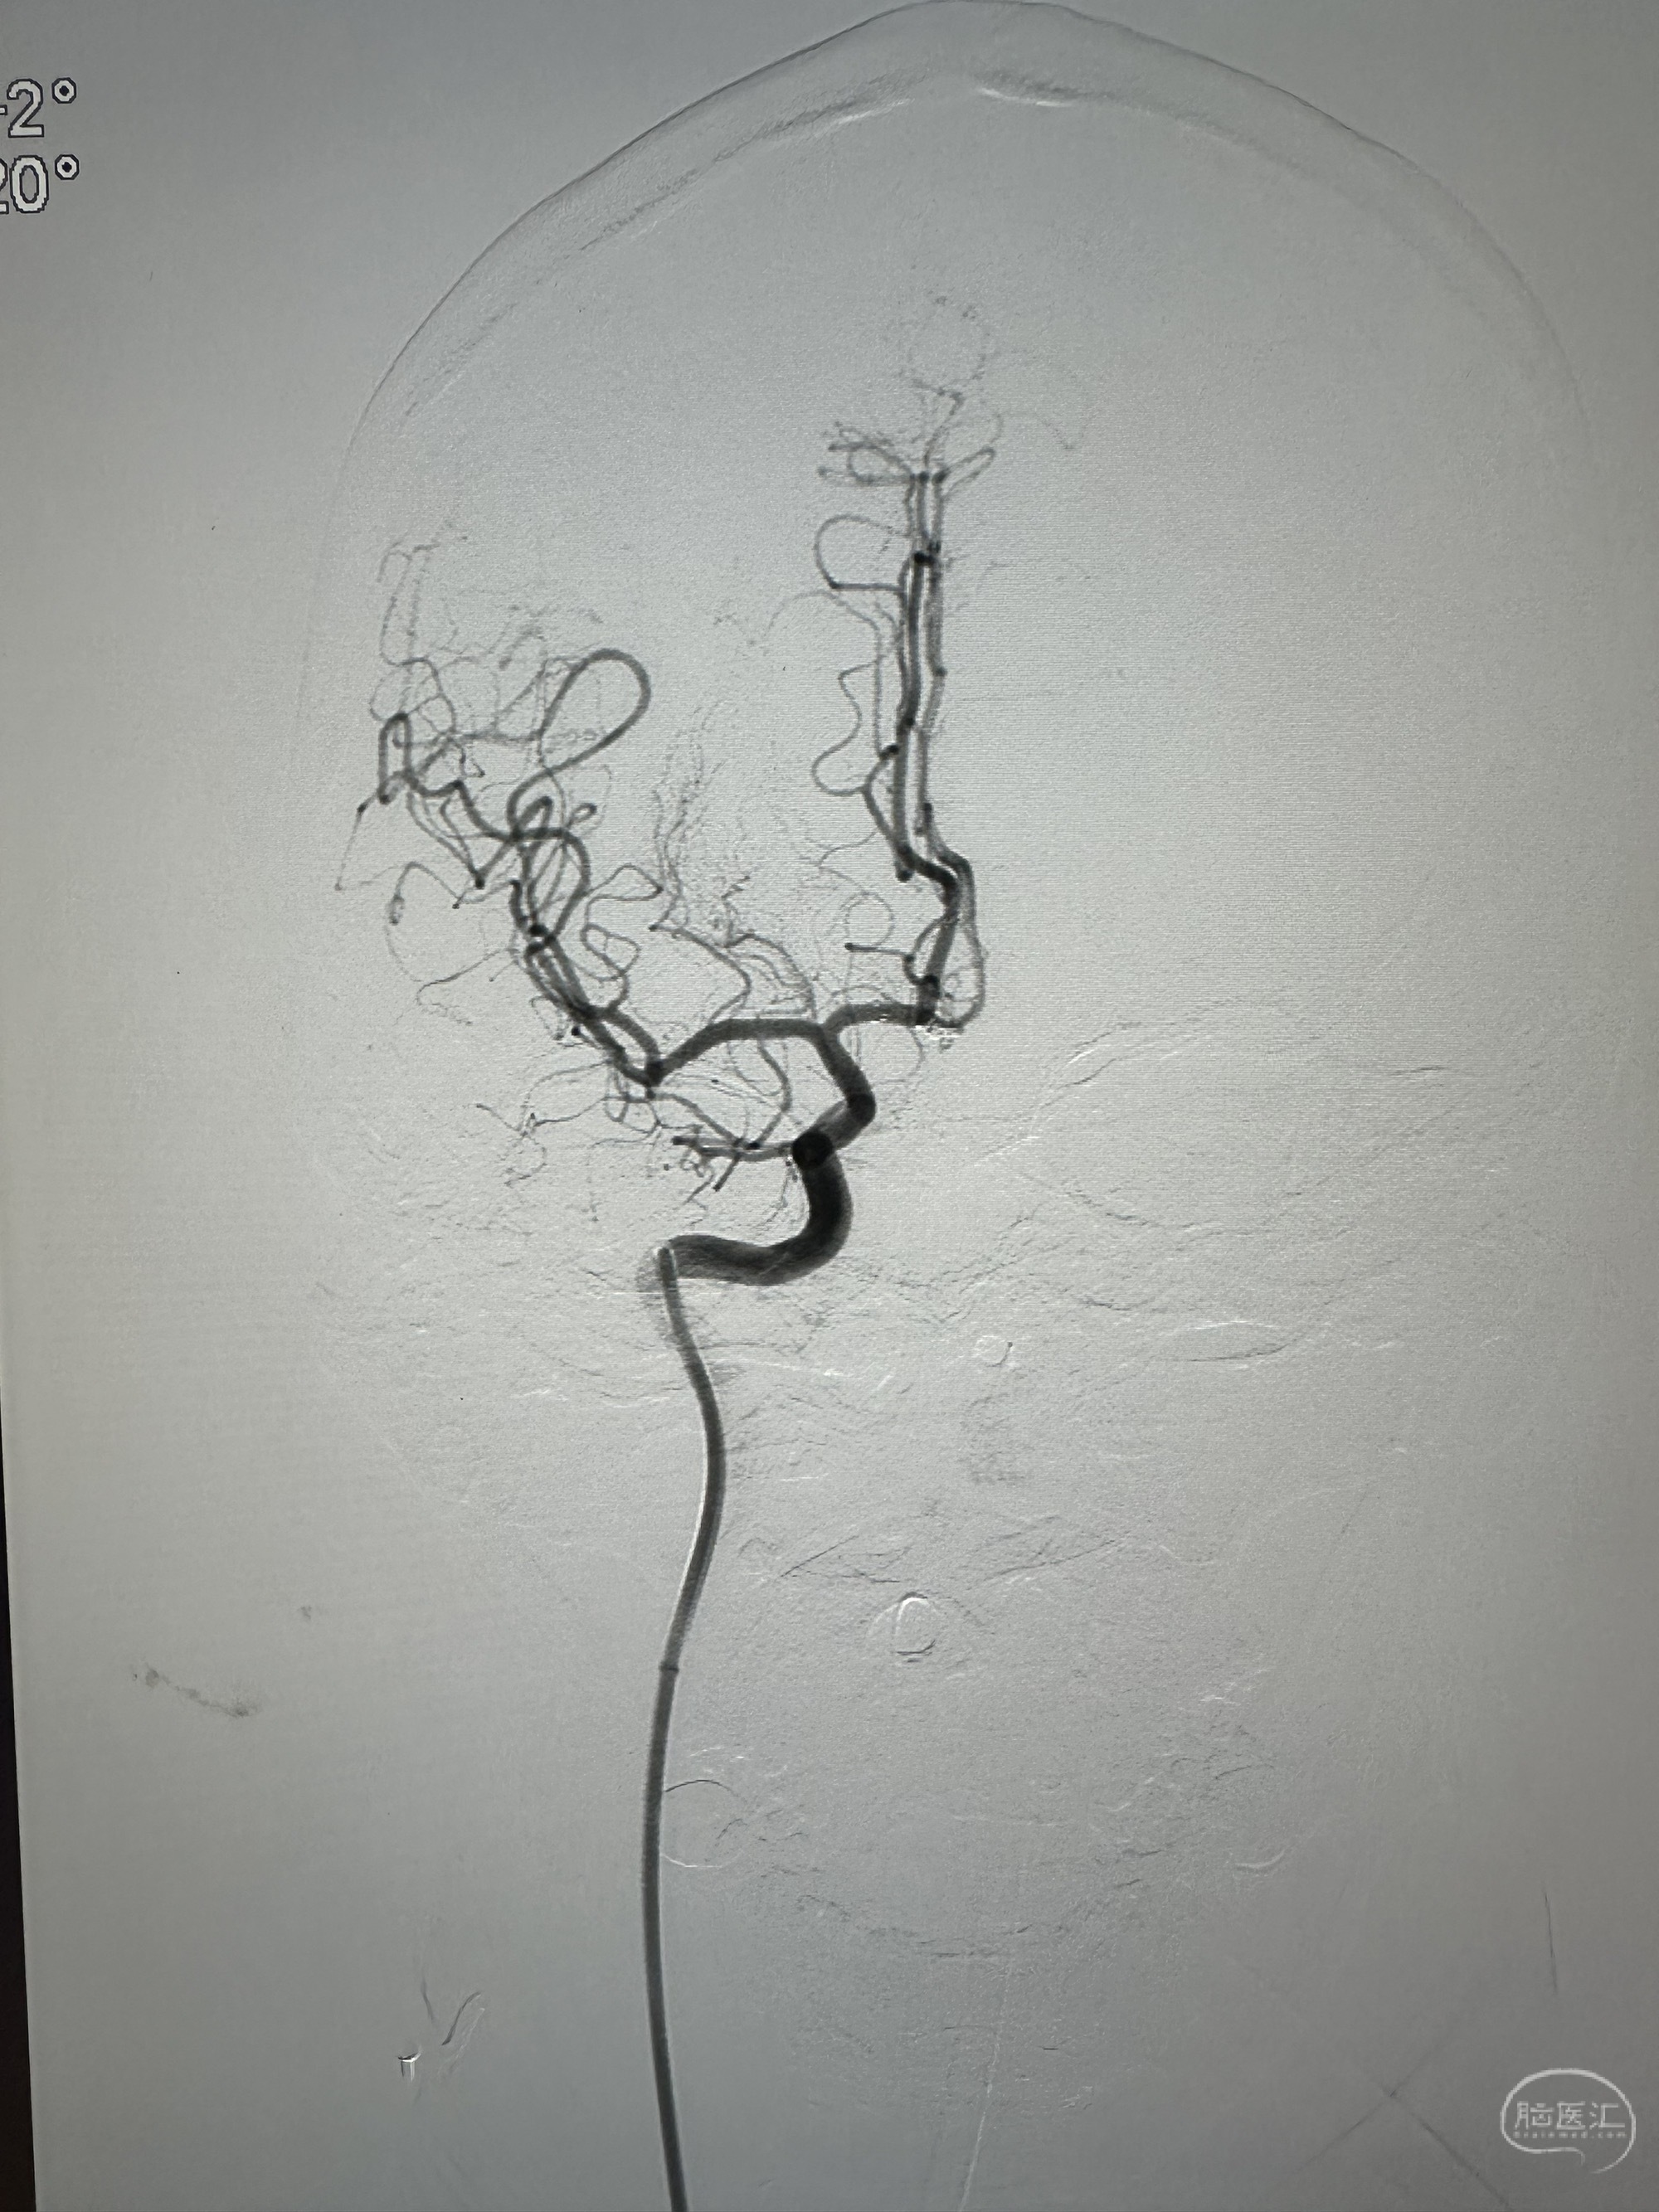

对侧造影

最后正位